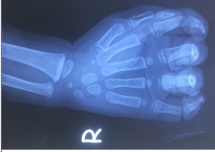

Bé gái bị đứt ngón tay do kẹt vào dây curoa máy rửa xe

Bé gái 23 tháng tuổi nhập viện trong tình trạng nhiều vết thương bàn tay phải, trong đó đứt gần rời ngón tay số 5 do bị kẹt tay vào dây curoa máy rửa xe.